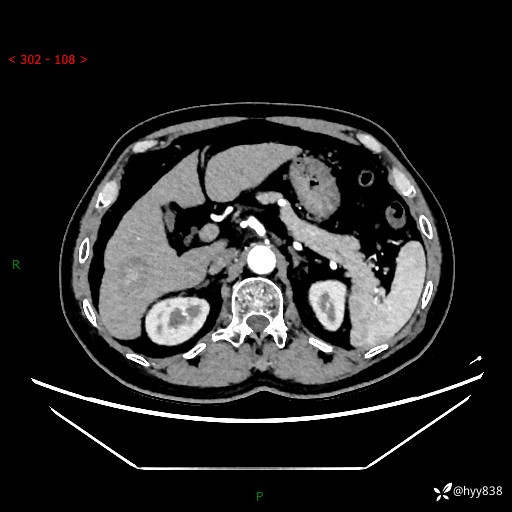

延迟期